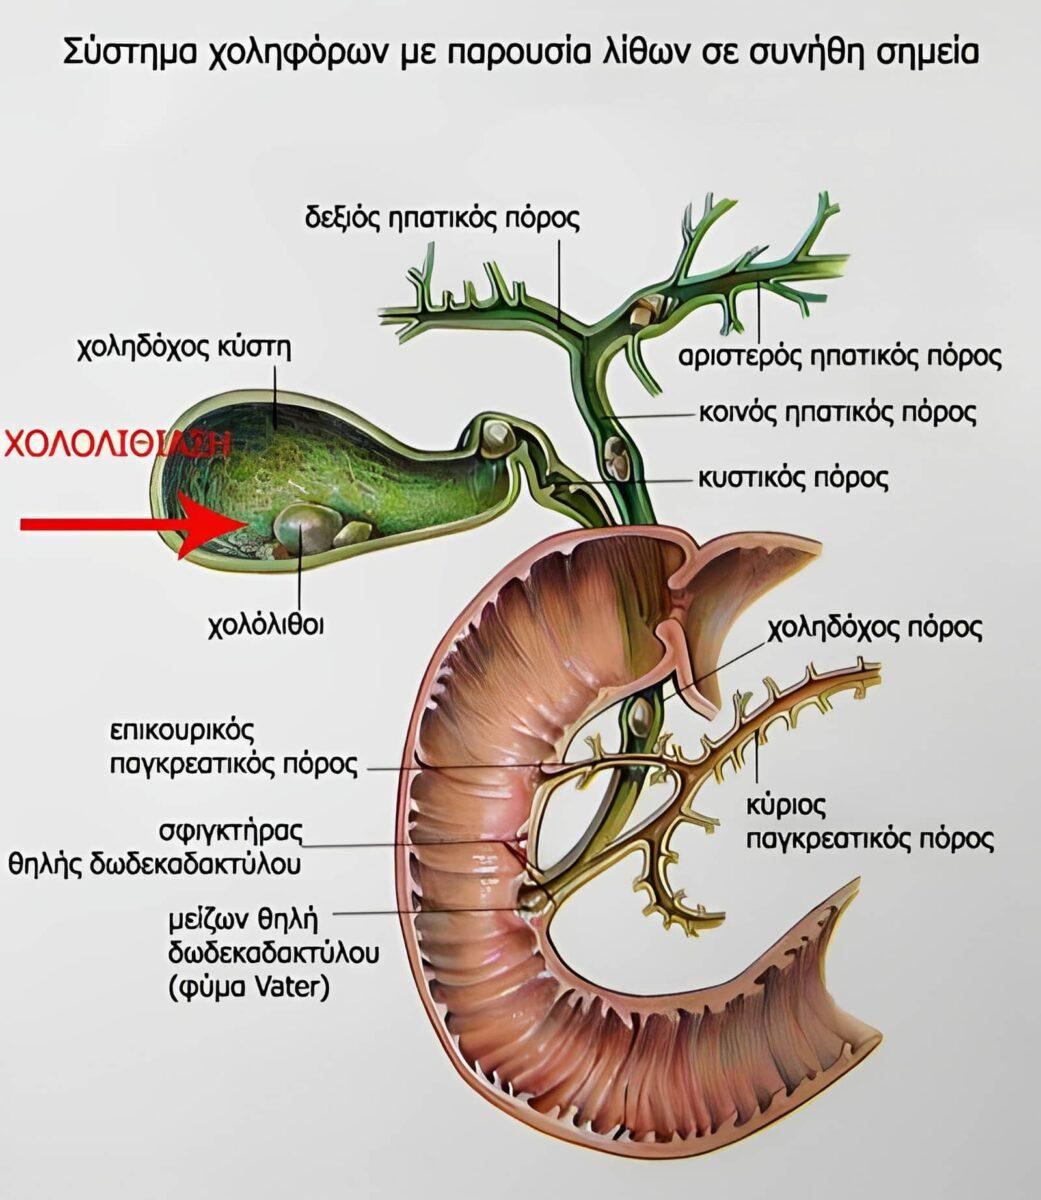

Η χοληδόχος κύστη, ένα μικρό όργανο που βρίσκεται κάτω από το ήπαρ, συνδέεται στενά με αυτό μέσω του χοληδόχου πόρου.

Όταν απολαμβάνουμε νόστιμο φαγητό, η χοληδόχος κύστη συστέλλεται, στέλνοντας τη χολή στο δωδεκαδάκτυλο για να βοηθήσει στη διάσπαση των λιπών. Η χολή έχει επίσης αντιβακτηριακές ιδιότητες, λειτουργώντας ως μια αόρατη αμυντική δύναμη της υγείας που διατηρεί την υγεία του πεπτικού συστήματος.

Η αναγκαιότητα αφαίρεσης της χοληδόχου κύστης εξαρτάται από τον τύπο των χολόλιθων και τη σοβαρότητα των συμπτωμάτων. Εάν οι πέτρες είναι μικρές και δεν προκαλούν σημαντική ενόχληση, οι γιατροί συστήνουν συνήθως συντηρητική θεραπεία με τακτική παρακολούθηση.

Ωστόσο, εάν οι πέτρες στη χολή προκαλούν σοβαρά συμπτώματα ή επιπλοκές όπως χολοκυστίτιδα, χολαγγειίτιδα ή εάν οι πέτρες είναι πολύ μεγάλες ή πολυάριθμες, οι γιατροί μπορεί να συμβουλεύσουν την αφαίρεση της χοληδόχου κύστης.

Κοινοί λίθοι του χοληδόχου πόρου

Μόλις αφαιρεθεί η χοληδόχος κύστη, ο κοινός χοληδόχος πόρος αναλαμβάνει το ρόλο του. Ωστόσο, χωρίς την χοληδόχο κύστη να αποθηκεύει τη χολή, η πίεση στον κοινό χοληδόχο πόρο αυξάνεται, προκαλώντας αντισταθμιστική διαστολή. Αυτή η παρατεταμένη στασιμότητα της χολής αυξάνει τον κίνδυνο εμφάνισης λίθων του χοληδόχου πόρου.